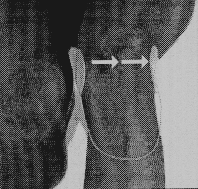

Bei Anwendung am Kniegelenk werden die Elektroden innen und außen jeweils auf den Kniegelenksspalt geklebt. In diesem Zusammenhang sollte erwähnt werden, daß die Pflasteranordnung so flach auf der Haut liegt, daß von den Patientinnen auch bei der Behandlung des Kniegelenkes Feinstrumpfhosen ohne Bedenken getragen werden können.